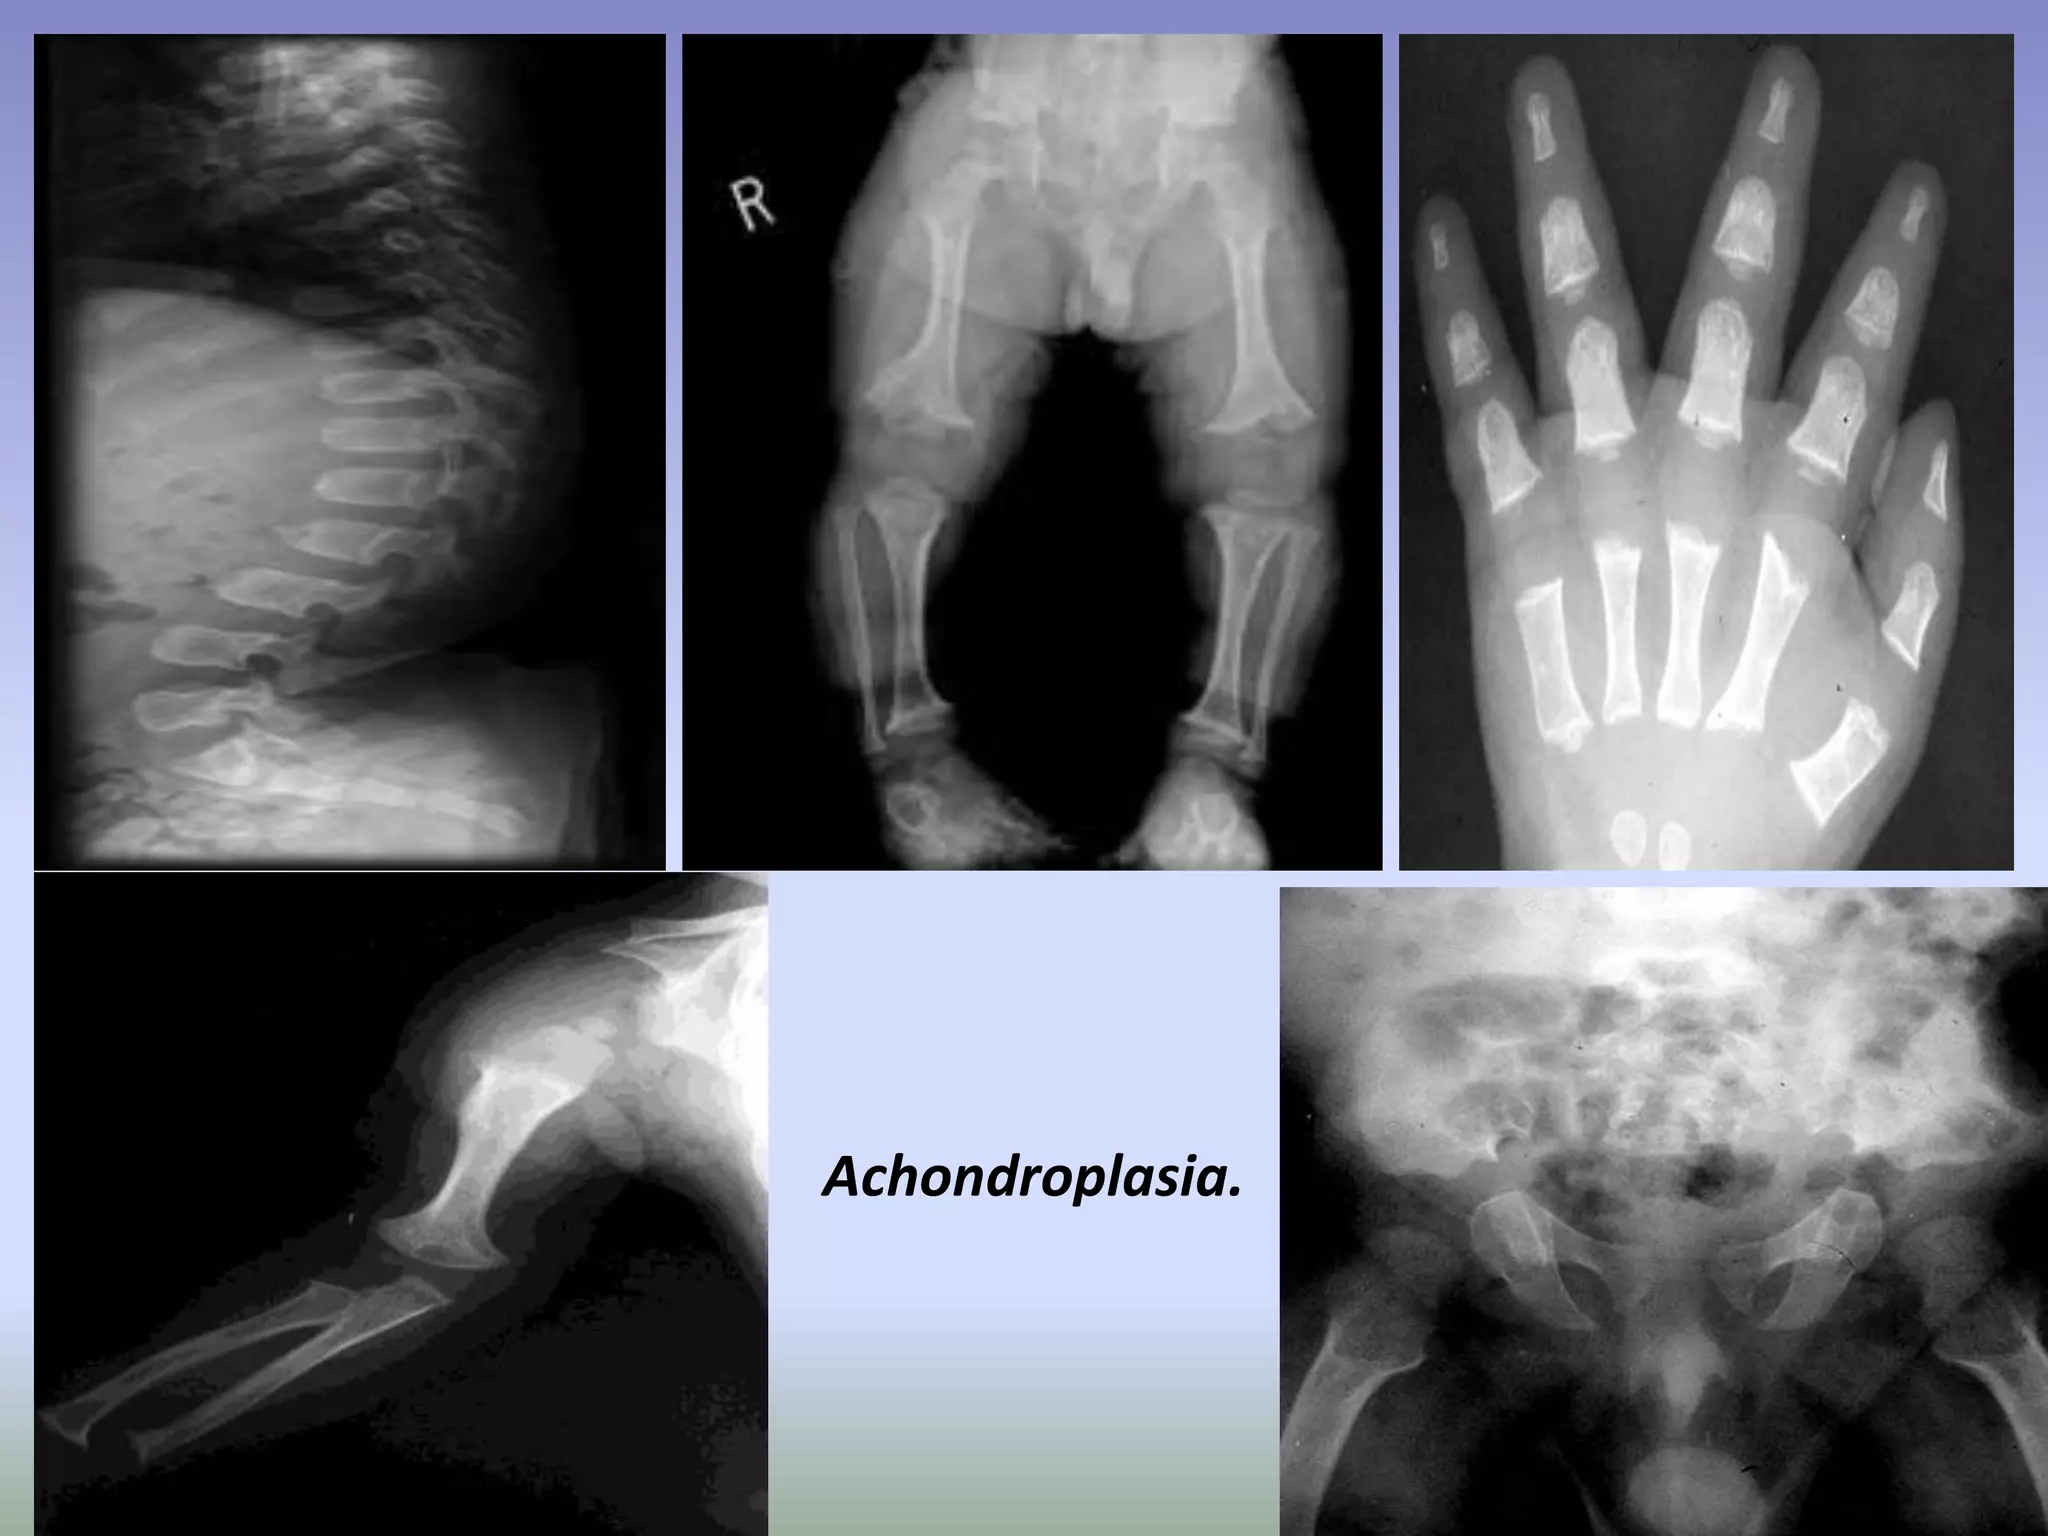

Achondroplasia.